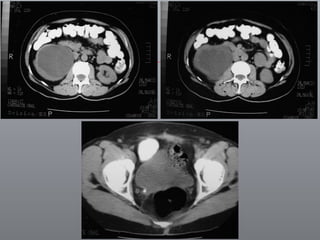

PRINCÍPIOS ONCOLÓGICOS ESSENCIAIS Princípios Robson O pedículo / anomalias / V. extranumerários Acesso e ligadura precoce da artéria / veias renais Remoção do rim / fascia de Gerota Remoção da glândula suprarenal ipsilateral Meticulosa linfadenectomia do diafragma / bifurcação da aorta

PRÉ-OPERATÓRIO ABORDAGEM DEPENDE DE Hand-assisted Transabdominal Retroperitoneal Sua experiência Patologia Anatomia